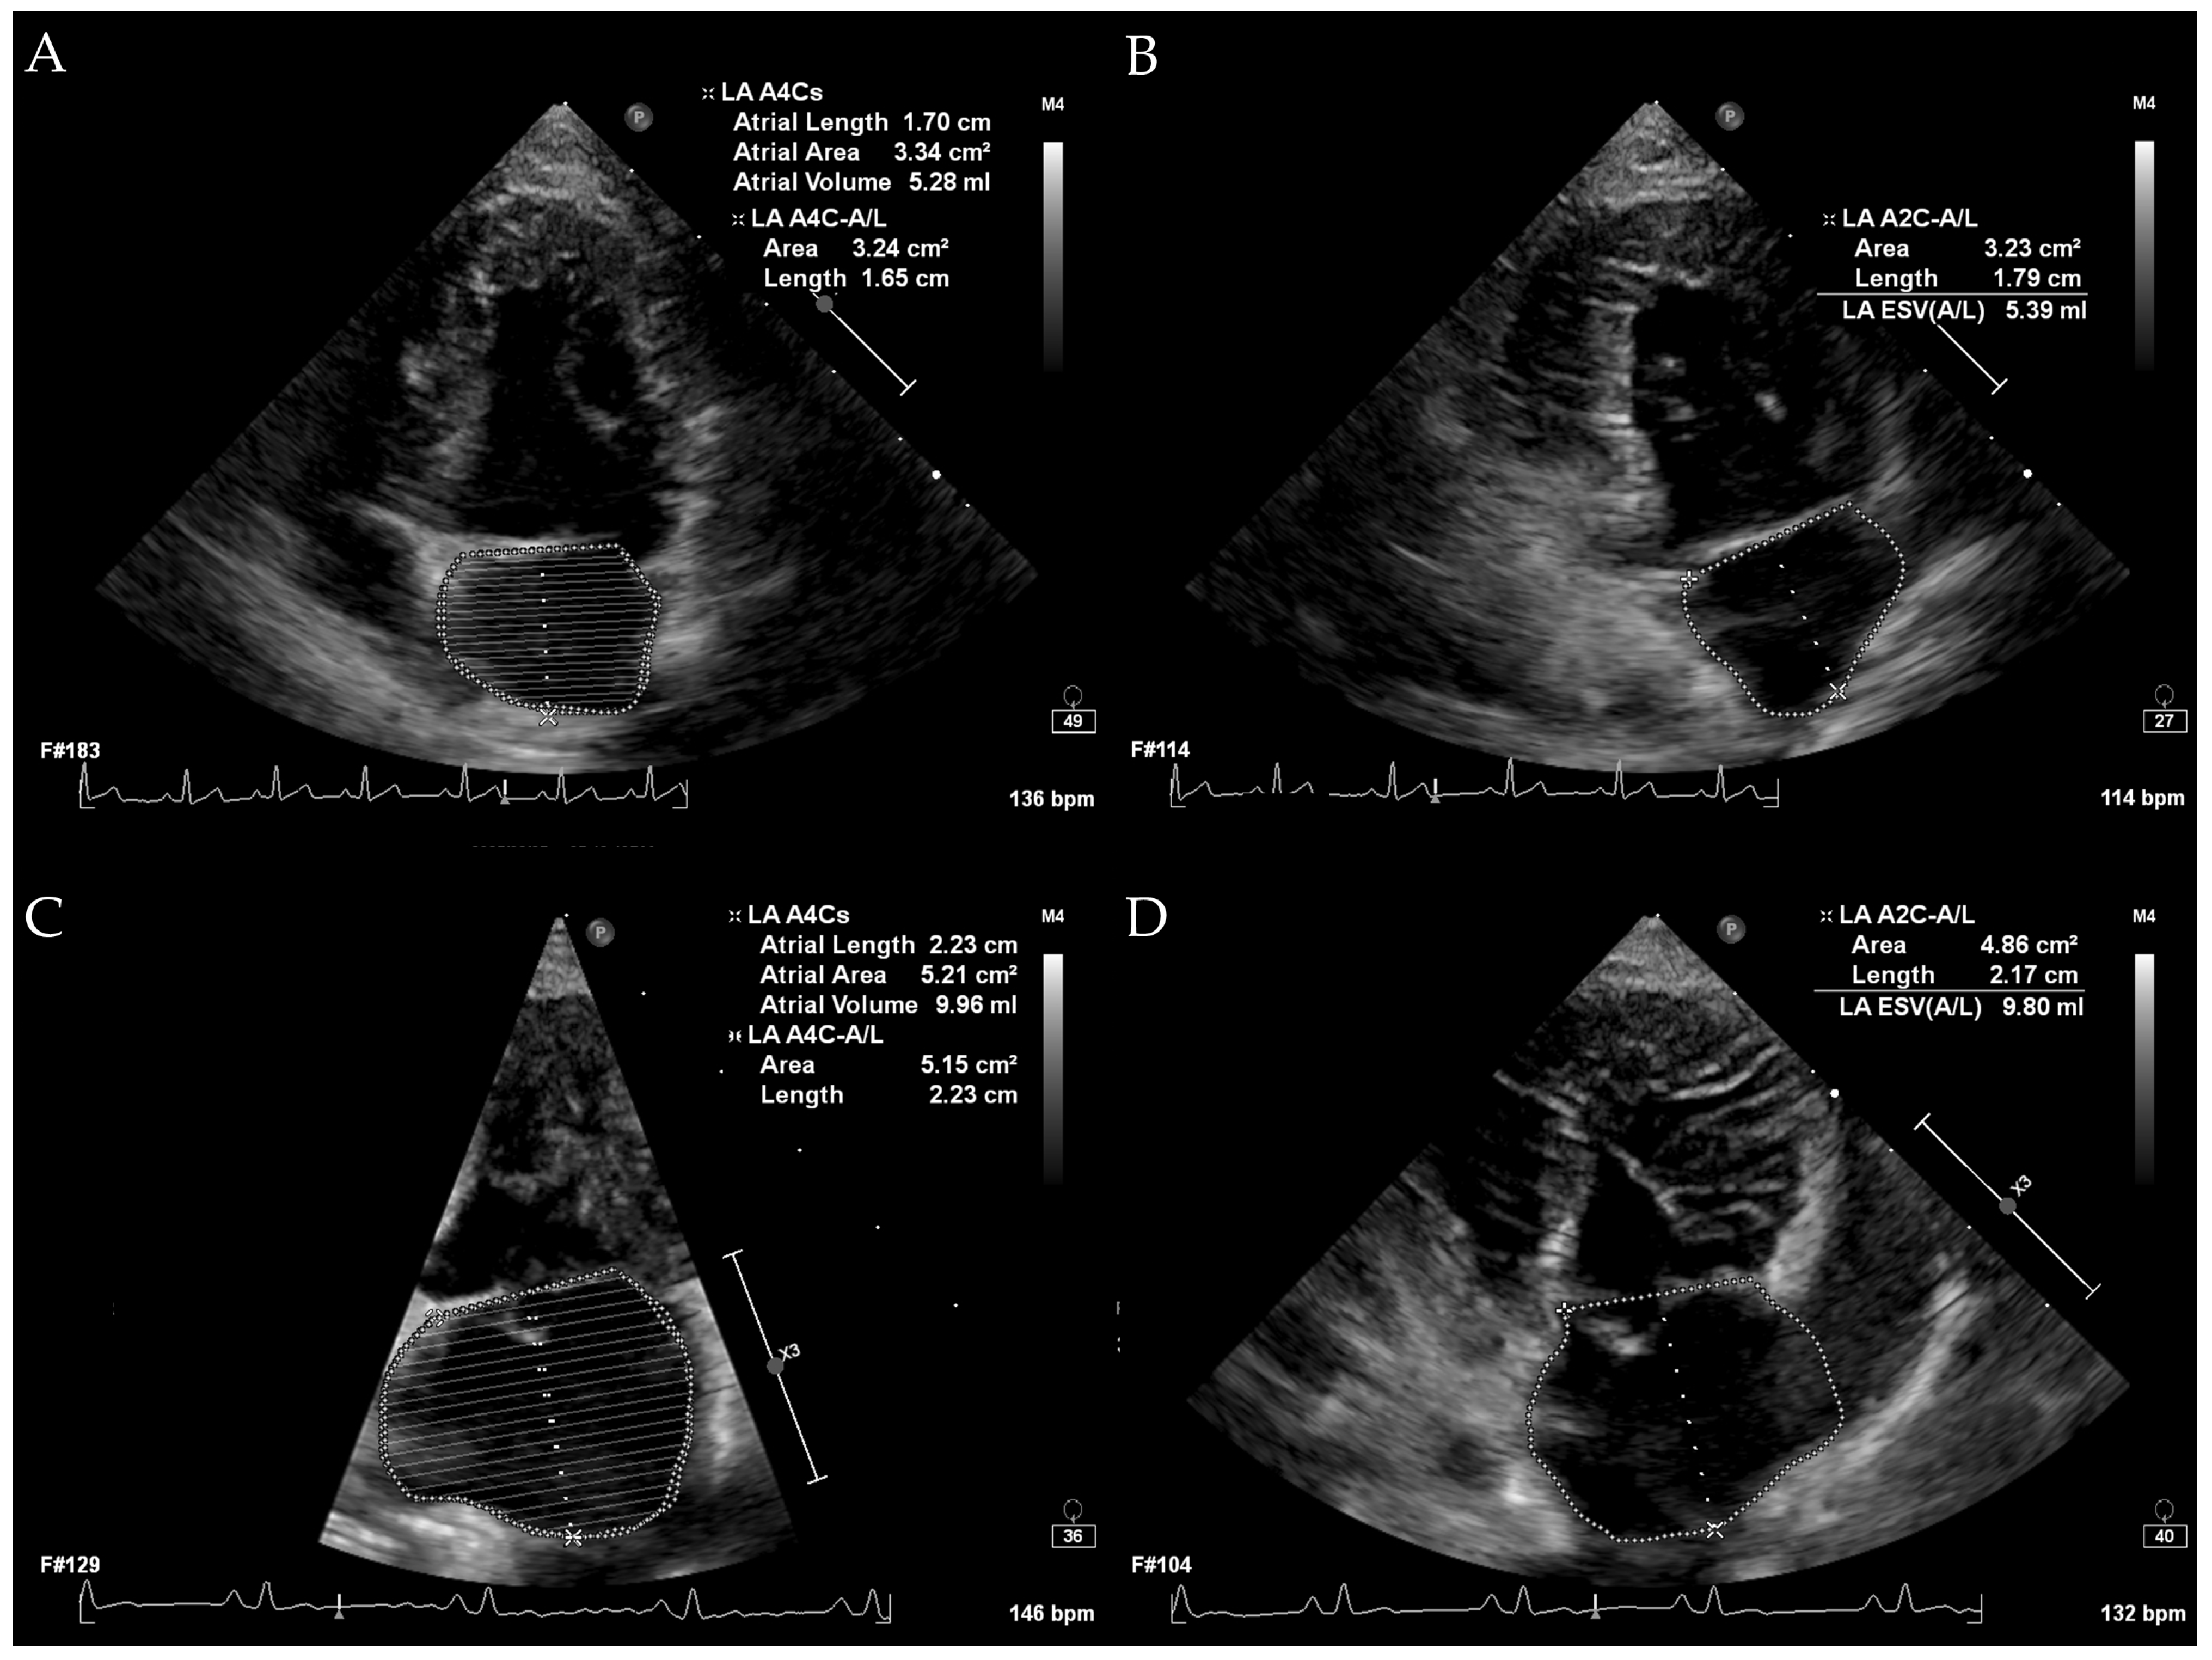

All echocardiographic examinations were performed using an EPIQ 7C ultrasound system (Philips, Bothell, WA, USA) equipped with a 3–8 MHz phased-array transducer by M.K and M.S. All procedures were conducted gently with manual restraint, and sedation with butorphanol was administered when necessary based on the patient’s condition. In cases of congestive pulmonary edema, diuretics were administered prior to echocardiography if clinically indicated. All echocardiograms were performed with continuous electrocardiography monitoring. Standard imaging planes included the right parasternal long-axis view, right parasternal short-axis view, left apical four-chamber view, and left apical two-chamber view. Additional views were obtained as needed. The 2-D, M-mode, pulsed-wave Doppler, continuous-wave Doppler, and color Doppler imaging were utilized according to the requirements of the examination. Normalized left anterior diameter (LADn), LA/Ao ratio, measured LVIDdN, and early diastolic transmitral flow (E peak) were measured from all dogs with both the measurement methods and scaling exponents based on previously published studies [4,20,21,22]. LA volumes measured by the monoplane SMOD method and the biplane area–length method were measured by tracing the endocardial border of the left atrium, carefully excluding the pulmonary vein and left atrial appendage, in left apical four-chamber view and left apical two-chamber view, one frame before mitral valve opening [19]. LA volume was calculated automatically by the built-in calculation formulas of the echocardiographic system. LA volume measurement is illustrated in Figure 1. LV volume was calculated using the monoplane SMOD in the left apical four-chamber view, one frame before mitral valve opening. All measurements were obtained as the average of three values, preferably from three consecutive cardiac cycles whenever possible.

Figure 1. Echocardiographic measurements of left atrial volume. (A) illustrates the measurement in a normal dog using the left apical four-chamber view. (B) shows the measurement in a normal dog using the left apical two-chamber view. (C,D) depict measurements in a dog with LA enlargement using the left apical four-chamber view and left apical two-chamber view, respectively. In all images, the LA endocardial border was traced, carefully excluding the pulmonary veins and the left atrial appendage.